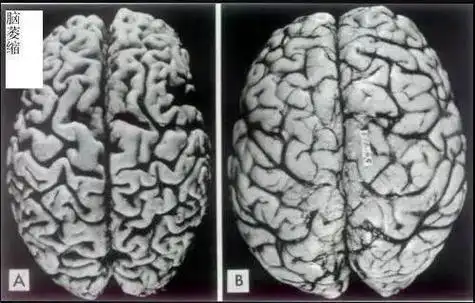

正常端脑 可以看到,酒精依赖患者的左,右大脑的灰质体积与健康对照